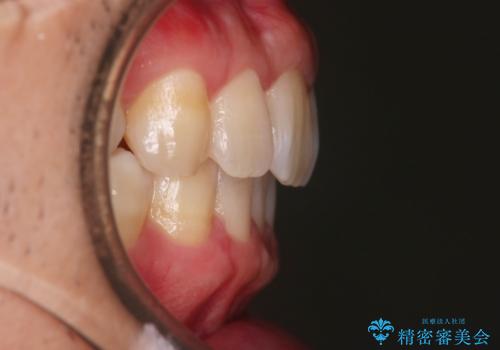

上の前歯が出ているという主訴が綺麗に改善されました。

その他の部位のがたつき、奥歯の噛み合わせも以前と比べると良くなっています。

目立たない装置で治療期間も10ヶ月と短く終了することができました。